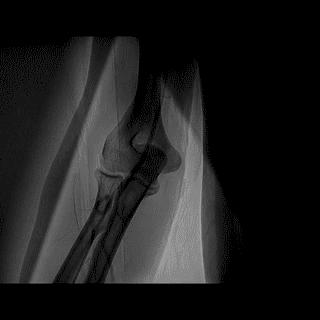

(4)LIMA桥血管造影

首选导管:JR4.0导管

其他导管:如果开口明显成角应选用专用的内乳动脉造影导管

➢ CASE 6

经股动脉途径TIG,非选择造影如果能清晰显影,可不做超选造影

➢ CASE 7

经左侧桡动脉途径JR4.0,非选择造影如果能清晰显影,可不做超选造影